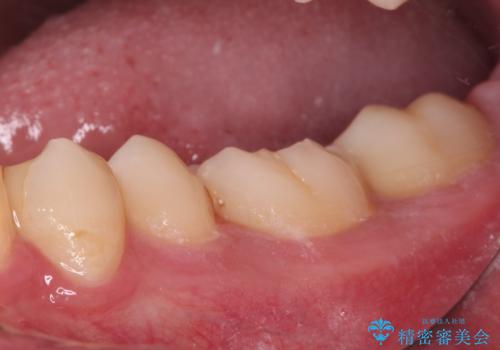

- 以前治療した詰め物が欠けてしまったことを主訴として来院した患者様です。

食べ物がはさまったり、冷たいものがしみるといった症状がみられました。

むし歯の染め出し液と拡大鏡を用いて、むし歯がないことを確認し、

セラミックインレーにて修復することとしました。